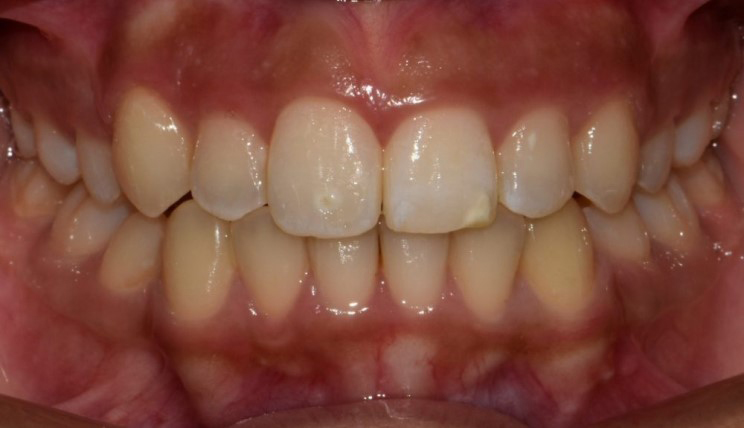

Chen chúc

Chen chúc là tình trạng có sự chênh lệch giữa kích thước răng và không gian có sẵn để sắp xếp răng trên cung răng.

Thông tin bệnh nhân:

Tuổi: 17

Giới tính: nữ

Lựa chọn điều trị Invisalign: Invisalign Comprehensive

Tổng thời gian điều trị:

29 tháng